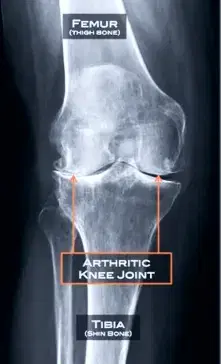

Arthritis is a condition that causes the degradation of the normally smooth cartilage that lines the knee joint. When the condition is severe it can lead to destruction of the underlying bone. This can manifest as bowing/deformity of the knee.

Arthritis is a disease with a spectrum of severity. At one end there is mild arthritis where the cartilage surface is rough or has cracks in it. At the other end of the spectrum there is severe arthritis where there is absolutely no cartilage left (“bone on bone”)

Specific images performed whilst the patient is weight bearing are the most accurate for identifying the loss of space between the bones, which indicates cartilage loss. Sometimes special x-ray views are required to demonstrate arthritis